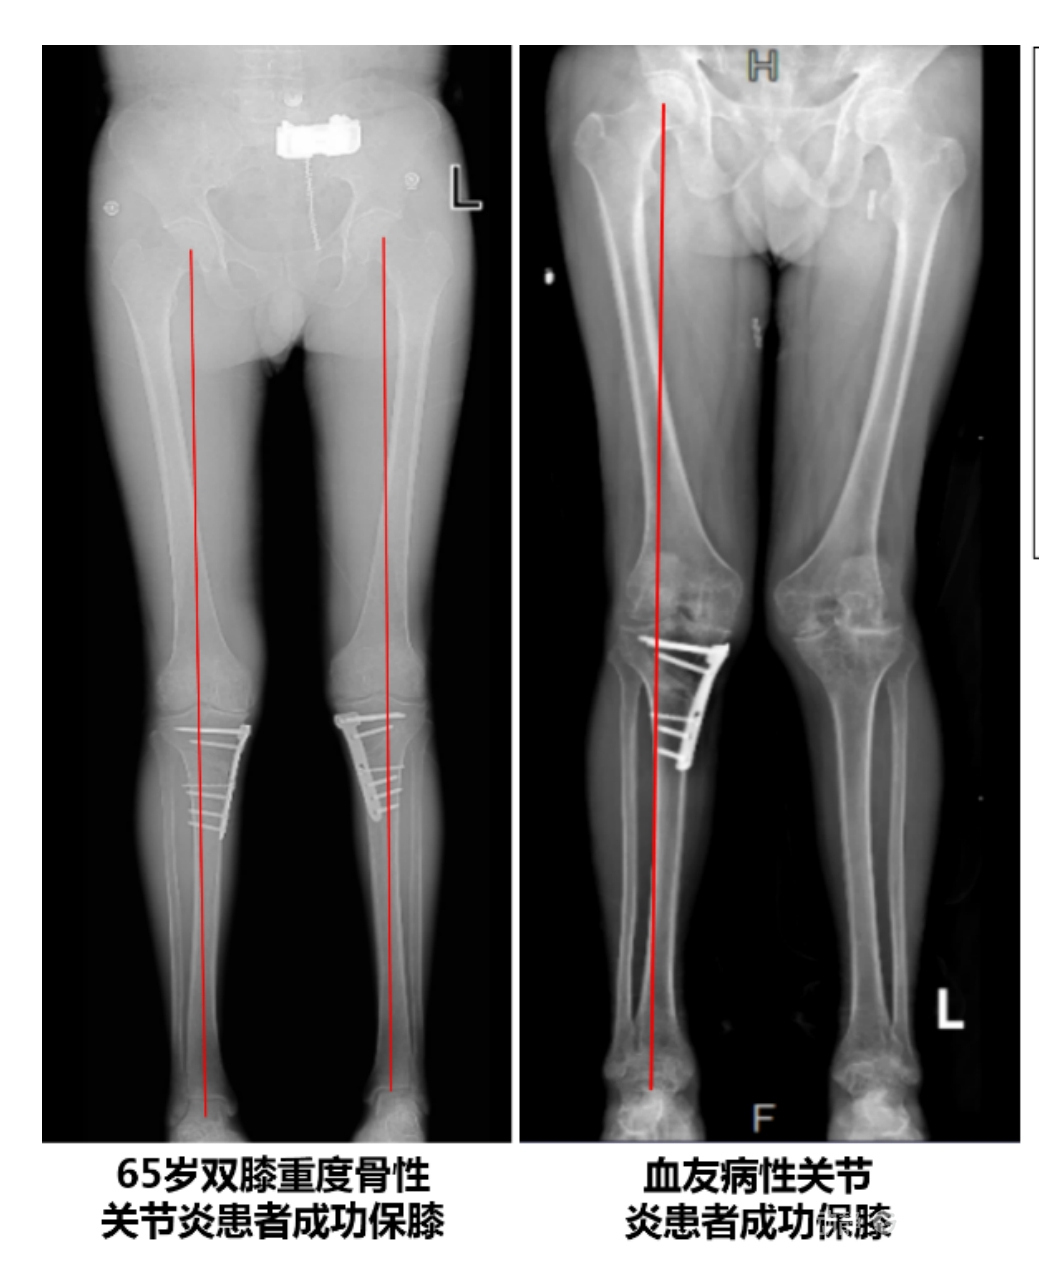

4.2 APTT-HTO脛骨高位截骨術

2025年7月,貴州醫科大學附屬醫院骨科團隊原創研發的腘肌前結節中脛骨高位截骨保膝術(Anterior Popliteus Transtibial Tuberosity-High Tibial Osteotomy, APTT-HTO)及其提出的脛骨結節分區與腘肌保護理論,登上了國際頂尖學術舞臺。該成果在全球最具影響力的專業會議之一——日本骨科協會第98屆年會上進行了兩次學術發言。[8]

該手術具有經皮微創、保留原生膝關節結構、符合階梯治療原則等優勢,通過調整下肢力線可促進部分軟骨再生,術后關節功能接近正常(如下蹲、爬山),患者還能從事中重體力勞動。相比其他術式,其有效規避了髕骨低位、血管損傷、合頁骨折等潛在并發癥。

目前,APTT-HTO技術已成功應用于千余名患者,幫助保留自身膝關節。此類保膝手術適用于單間室膝關節炎患者(如 “羅圈腿”),核心是通過調整力線糾正畸形,減輕磨損間室壓力、發揮健康間室作用,延長膝關節壽命。若出現膝關節疼痛、保守治療無效且X線顯示關節間隙部分狹窄,建議及時就醫評估是否適合手術。